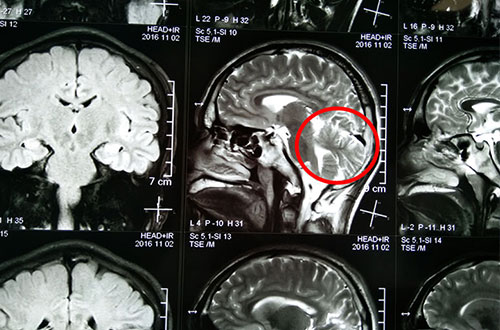

术前影像资料:红圈内为异常信号灶

术前影像资料:红圈内为异常放电区

11月2日行MR头颅平扫+SWI,灰白质对比成像示:双侧枕叶异常信号伴脑白质量减少。